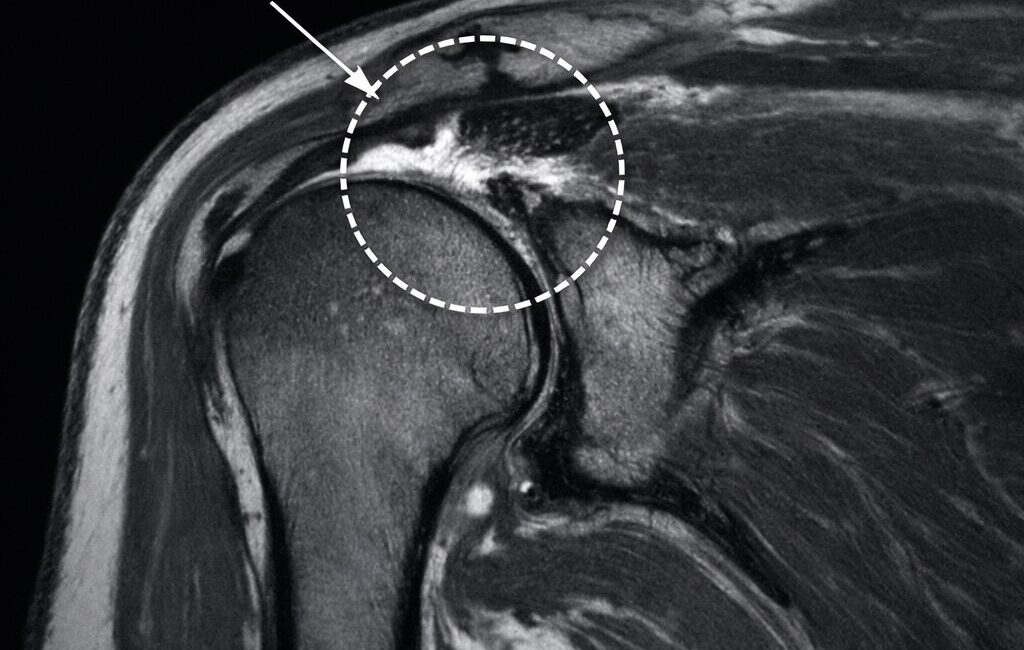

- 585 had MRI abnormalities of their rotator cuffs

- 62% had partial tears and

- 11% had complete tears of their cuffs.

- Of the 70 people with full tears, 37% had full tears in BOTH SHOULDERS

- Rotator cuff abnormalities were seen in 96% of those without symptoms and 98% in those with symptoms.

- Just as confusing was that the prevalence of tendinopathy and partial tears had zero difference between those with and without pain.

- Even in the 96 full tendon tears, 78% were in shoulders of people with NO SYMPTOMS.

Of the total study, 99% of people aged 41 and older had at least 1 rotator cuff abnormality on MRI.